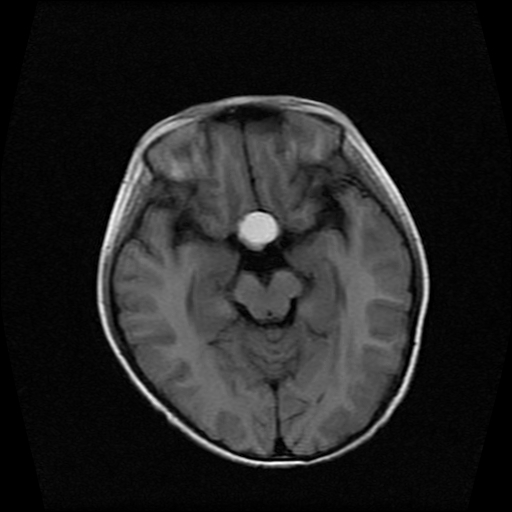

男性,12岁。反复头痛呕吐半月。脑积液无异常。病变部位ct值32hu,dwi无异常。

鞍上为主,累及鞍内,垂体受压位于鞍底。mri呈短t1、长t2信号,不太支持生殖细胞肿瘤,首考颅咽管瘤。

鞍内囊性占位性病变,t1wi、t2wi,均为高信号影。ct平扫为等密度。发病年龄较小。故首先考虑颅咽管瘤,可以做ct增强扫描